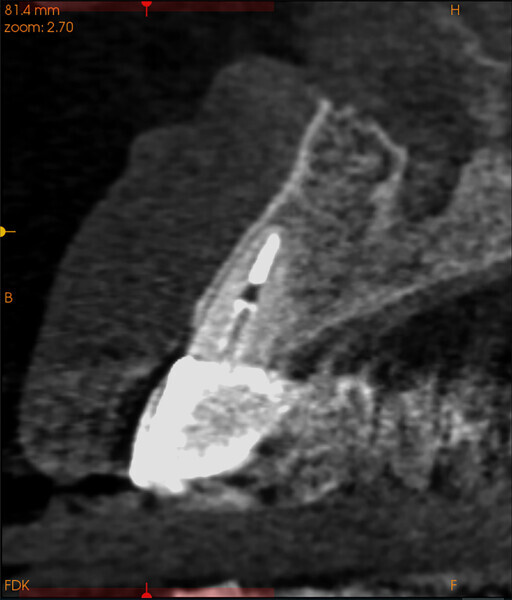

Fig. 14a:

The CBCT cross-sectional image revealed a favourable pre-op condition for a PET procedure.

Fig. 14b: Using the native Carestream 3D Imaging Software,

a simulated implant (red outline) and abutment projection (yellow outline) was positioned within the available bone to avoid the root fragment.